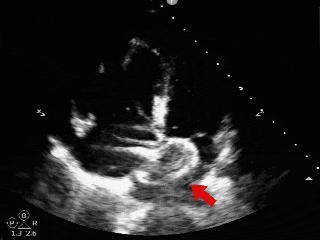

术前超声

超声描述:右房室较大,左房室不大。房间隔中部可见中断,约14x16mm。缺损边缘较硬,二尖瓣侧缘、后上缘分别为16mm、8mm,主动脉侧缘、后壁缘分别为0mm、10.7mm,上、下腔静脉侧缘分别为16、14mm。十字交叉存在。房间隔长度43mm。M型二尖瓣呈双峰,前后叶逆向,E-E间距相等。

CDFI:房水平可见一股红色彩流由左房经缺口进入右房。主动脉瓣下左室流出道探及微量舒张期反流信号。三尖瓣口右房侧探及微量收缩期反流信号,Vp 2.7m/s,PG 29mmHg。二尖瓣口左房侧探及微量收缩期反流信号。

超声提示:

-

先天性心脏病。

房间隔缺损(继发孔型)。

左心收缩功能在正常范围。